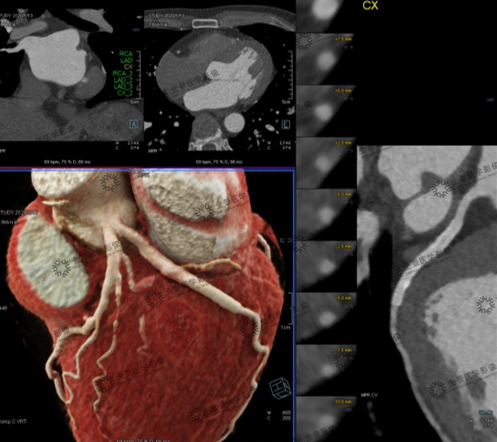

男,54岁,冠心病PCI术后,原始图像结合二维MPR及三维CVRT图像清晰显示,左回旋支CX近中段支架壁光滑、形态正常,支架通畅。